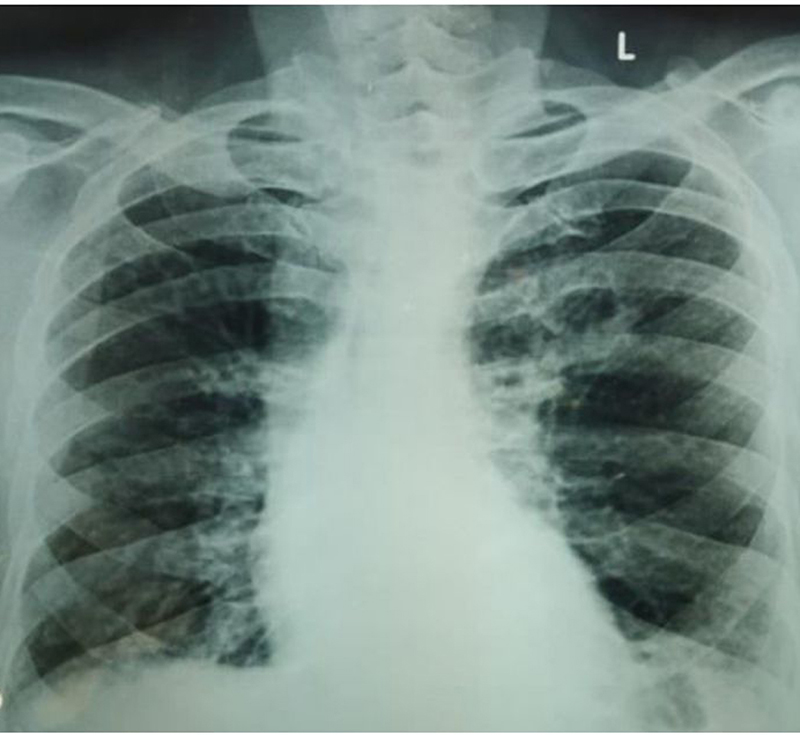

Figure 1

Figure 1. Cavity in left mid zone at time of ATT initiation.